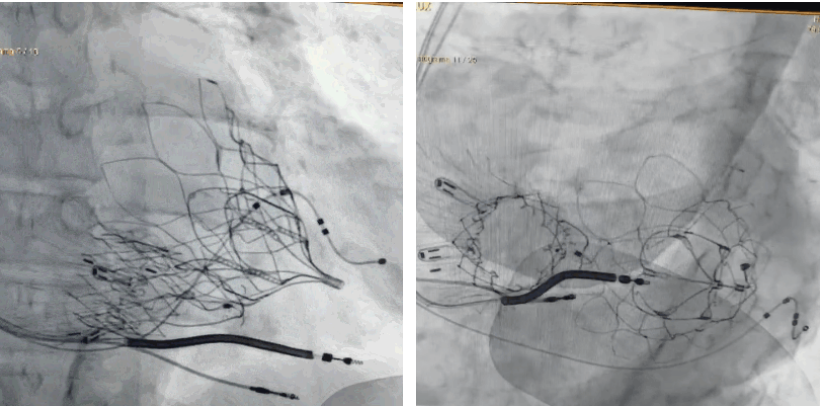

術(shù)后DSA顯示Lux-Valve Plus與Tendyne和ICD無(wú)相互影響

術(shù)后超聲顯示僅殘余微量瓣周漏

LuX-Valve Plus經(jīng)血管三尖瓣置換系統(tǒng)此次“出海”圓滿完成,術(shù)后Rodrigo Estévez-Loureiro教授對(duì)LuX-Valve Plus經(jīng)血管三尖瓣置換系統(tǒng)的器械性能和治療效果大為稱贊,認(rèn)為L(zhǎng)uX-Valve Plus的手術(shù)體驗(yàn)非常好。術(shù)后即刻超聲顯示三尖瓣反流幾乎完全消失,血流動(dòng)力學(xué)改善顯著,患者恢復(fù)快。在面對(duì)復(fù)雜解剖結(jié)構(gòu)、超聲影像質(zhì)量不佳、有起搏導(dǎo)線干擾時(shí),Lux-Valve Plus也體現(xiàn)了極強(qiáng)的適應(yīng)性。Thomas Modine教授和Anson Cheung教授也肯定了LuX-Valve Plus術(shù)中操作的便捷性,認(rèn)為L(zhǎng)uX-Valve Plus容錯(cuò)率高,對(duì)術(shù)中影像的依賴較小,后期希望可以更多的應(yīng)用LuX-Valve Plus三尖瓣置換系統(tǒng)于臨床實(shí)踐,讓更多的三尖瓣重度反流患者盡早獲益,改善預(yù)后。